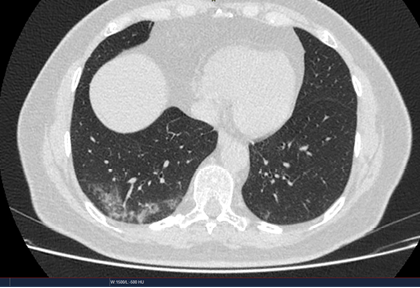

Routine clinical laboratory assays were performed in the hospital’s clinical laboratories. Clinical and laboratory information was extracted from the patients’ medical records. C reactive protein (CRP) in plasma was measured by immunoturbidimetry (Beckman Coulter, Krefeld, Germany). Interleukin-6 (IL-6) levels in plasma were measured by electrochemiluminescence (Siemens Medical Solutions Diagnostics, Siemens Healthcare, Erlangen, Germany). CT scans were read by experienced radiologists who scored results by severity using the criteria shown in Figure 1.

Figure 1. Clinical assessment of pneumonia severity based on computed tomography (CT) scores.

Scoring method: Mild (CT-1)—no more than three ground-glass opacities of <3 cm maximum diameter. Moderate (CT-2)—more than three ground-glass opacities; less than 50% involvement by visual assessment. Medium-heavy (CT-3)—ground-glass opacities and pulmonary consolidation; 50-70% involvement by visual assessment. Severe (CT-4)—diffuse ground-glass opacities with or without consolidation; more than 75% involvement by visual assessment.